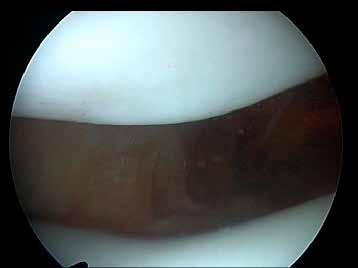

In patellar maltracking, which is usually lateral maltracking, rather than the patella sitting in the groove it tracks over the lateral femoral condyle, on occasions it can be seen to actually overlap the femoral condyle. When the patella tracks in this way it touches the femoral condyle causing pain. So someone with patellar maltracking would have considerable pain in the knee joint as they kneel or in any activity that requires flexion of the knee joint. The pain of the condition makes activities of daily living difficult. The constant wear of the patella on the lateral femoral condyle initially leads to cartilage

damage, followed by erosion and loss of the cartilage finally with the wear of bone on bone to eburnation. Figure below, Siddiqui (2013), patellar maltracking as the knee joint is bent from 0 through to 90 degrees.

Normal patella tracking

Arthroscopic views of maltracking patella as the knee is flexed (Siddiqui 2013).